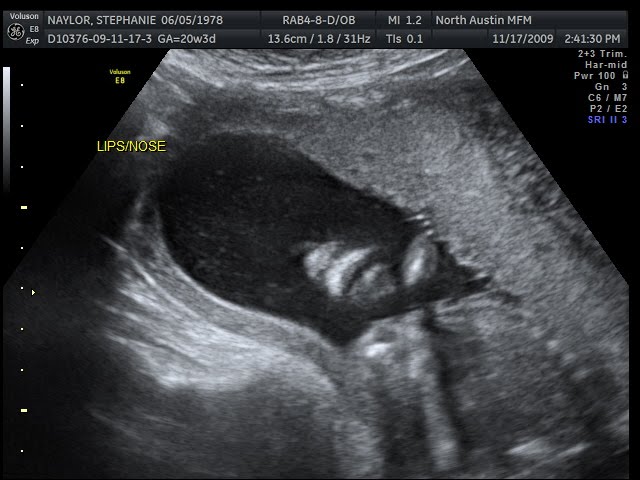

Here's a good picture of Lumpy's nose and mouth.